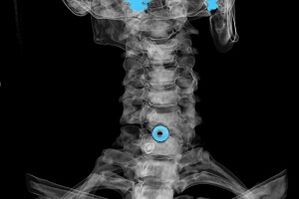

The diagnosis is established on the basis of characteristic symptoms, as well as using:

- X-ray. The method is ineffective, especially in the late stages of the development of osteochondrosis.